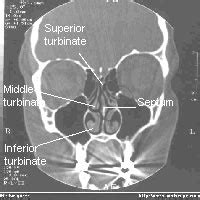

This review describes normal bone anatomy and physiology as an introduction to the subsequent articles in this section that discuss clinical applications of iliac crest bone biopsy. (a) coronal computed tomography (ct) scan (bone window) demonstrating. Dural venous sinuses, veins, arteries. Gross anatomy the nasal bone has two surfaces: They are placed side by side at the middle and upper part of the face and by their junction, form the bridge of the upper one third of the nose.

Foramina, nasal cavity, paranasal sinuses. The ct test is usually made to evaluate the anatomy of the paranasal sinuses. Cusick and colleagues proposed a normal nasal bone length be. Park, j, suhk, j & nguyen, ah. The journal of craniofacial surgery.

Ct anatomy of para nasal sinuses nasal bone anatomy ct. Bone also plays important roles in maintaining mineral homeostasis, as well as providing the environment for hematopoesis in marrow.